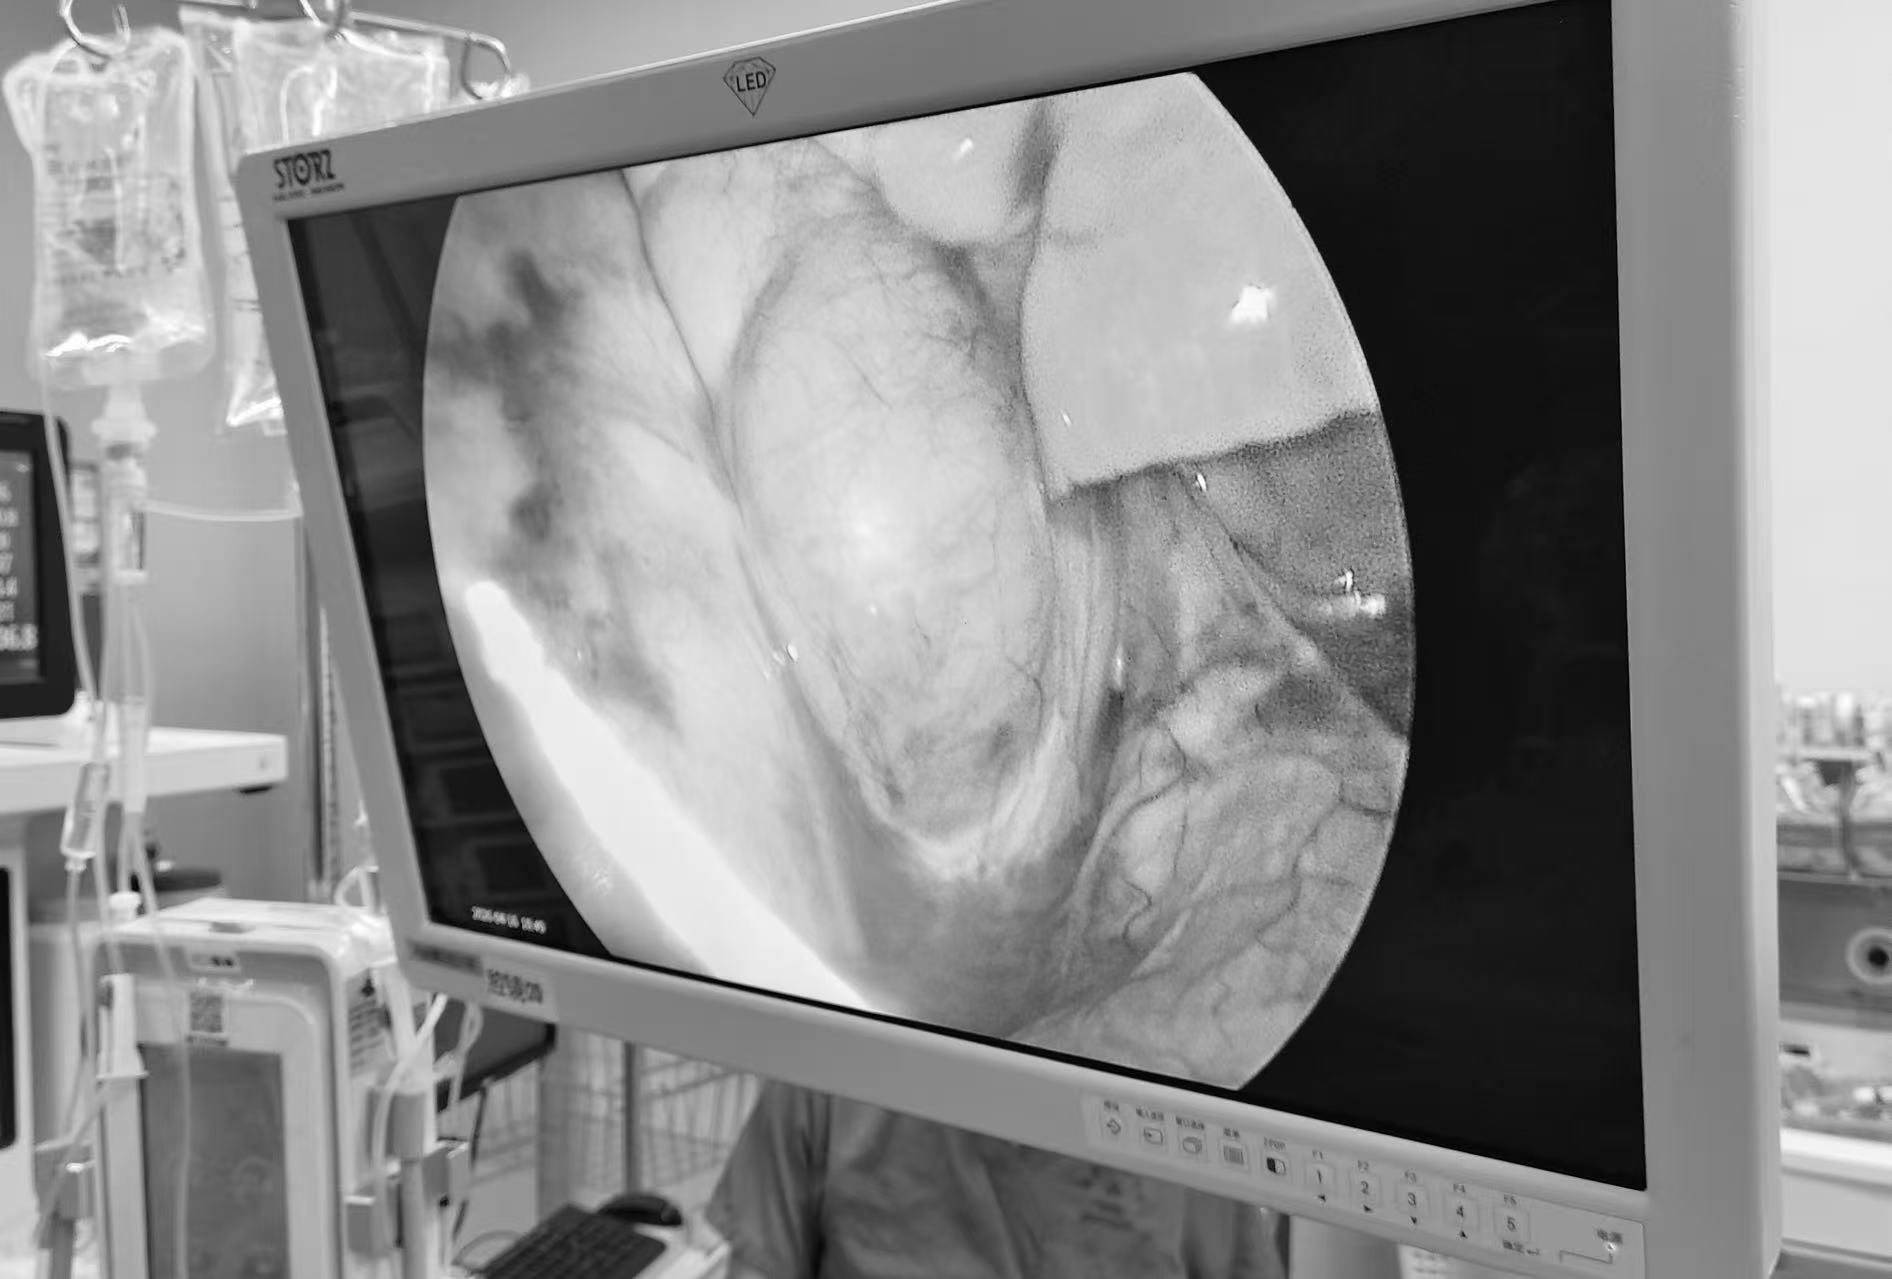

16日,手术如期进行。全麻、气管插管、动静脉穿刺置管…… 麻醉团队精准把控着孩子的生命体征,为手术筑牢第一道安全防线。随后,主刀医生带领团队,在孩子右侧腋下做了4个仅约 0.5 厘米的微小切口,置入胸腔镜器械,开始了这场“刀尖上的舞蹈”。镜头下,黄色的分叶状肿物几乎填满了右侧胸腔,奇静脉弓被肿物紧紧包裹,分离时每一步都如履薄冰。团队凭借丰富的经验和精准的操作,小心翼翼地用超声刀和电凝钩,一点一点游离纵隔胸膜,保护好纵膈内的重要器官,最终胸腔镜微创下完美切除肿块。

术中巨大肿块